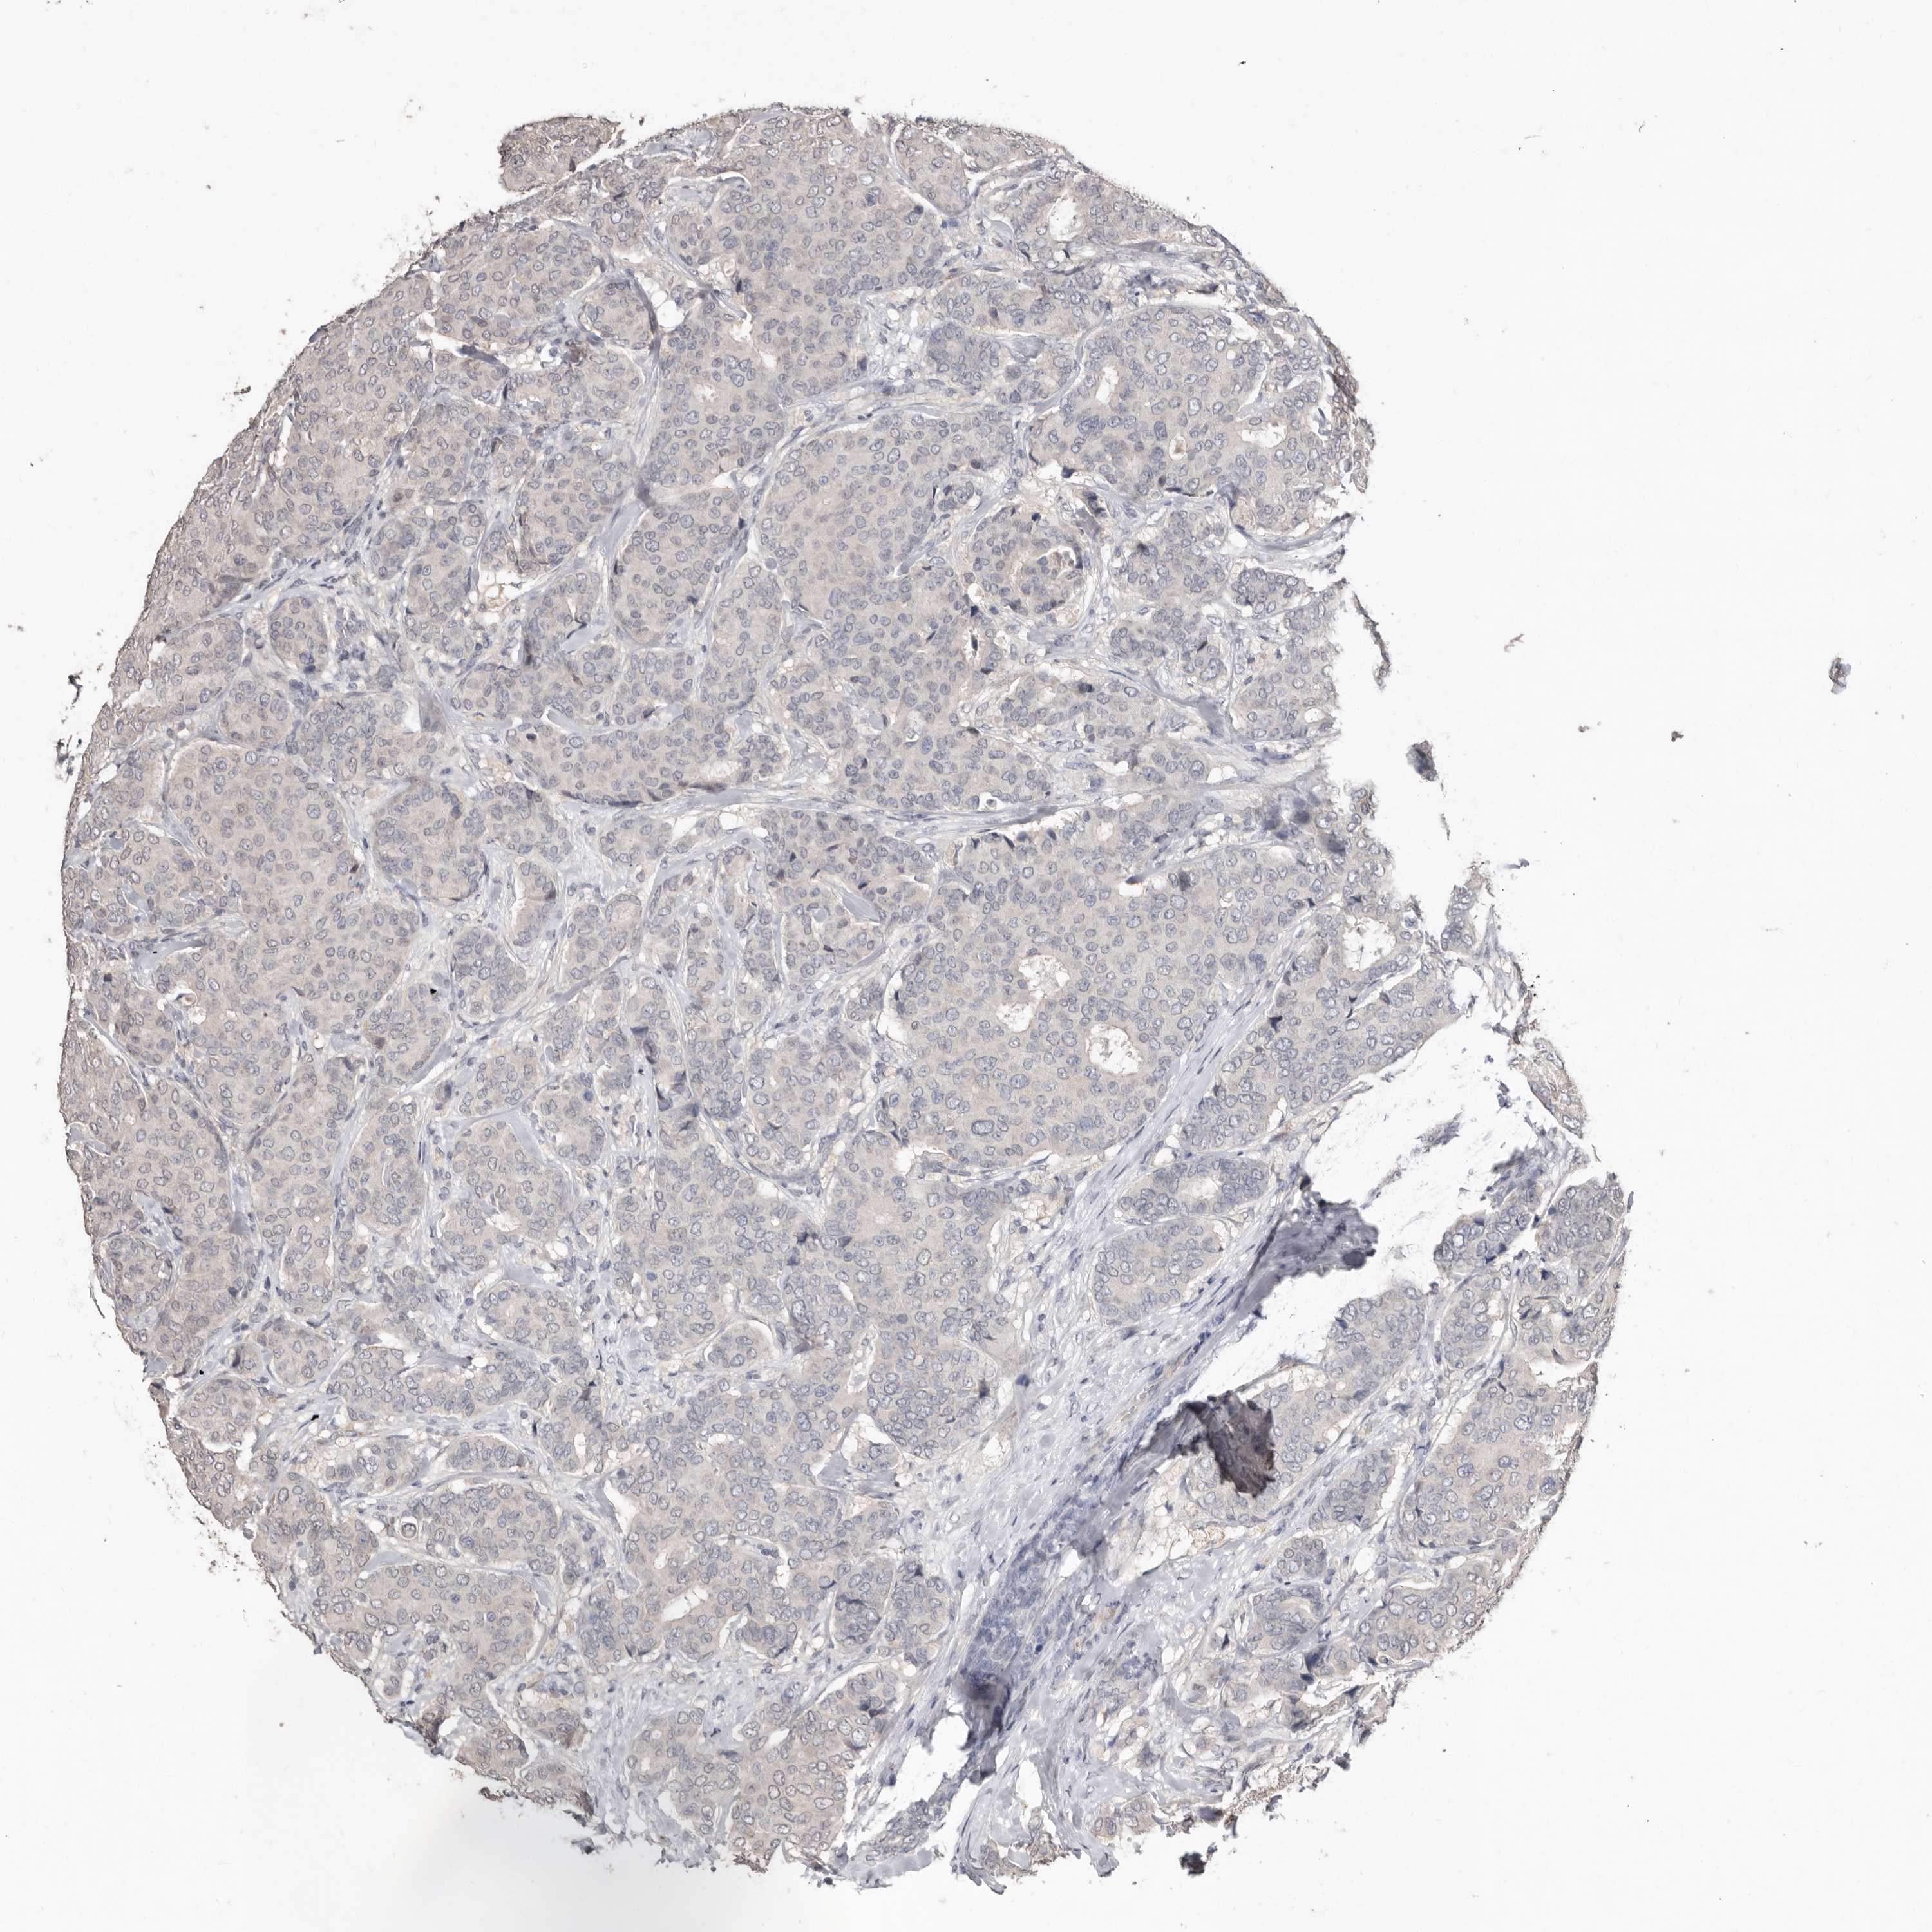

BRCA TCGA BRCA VALIDATION PROTEIN EXPRESSION